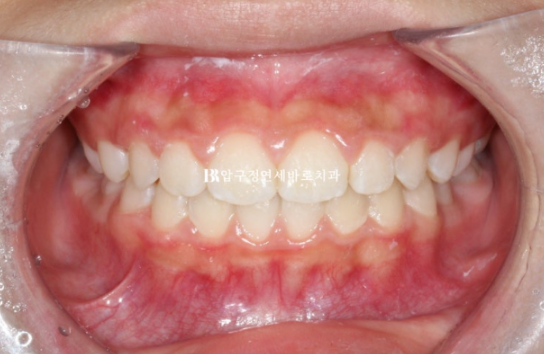

24.12

다행히 한달만에 배열이 잡히고 중심선은 잘 맞으며 측절치도 잘 내려왔습니다.

교합이 좋지 않으면 교정을 마무리 짓지 않습니다.

어린이 교정이지만 결과가 성인교정 결과에 준하는 만큼 철사 유지장치도 성인교정에 준하게 들어갑니다.

교정 종료 시점 유치는 아직 3개가 남았습니다.

전 후 비교 보겠습니다.

치료 기간은 1년 2개월입니다.

23.10~24.12

뻗쳐있던 앞니 각도가 개선이 되면서 돌출이 해소가 되었습니다.